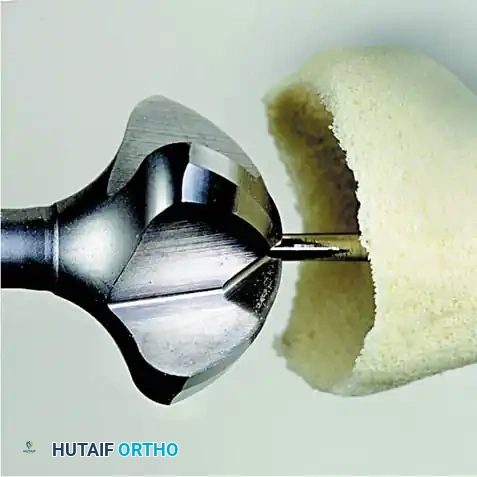

2. Joint Preparation: The capsule is incised, and the collateral ligaments are released. The severely eroded articular surfaces of the first metatarsal head and the base of the proximal phalanx are resected. Cup-and-cone reamers are highly recommended to preserve length while allowing multi-planar adjustment.